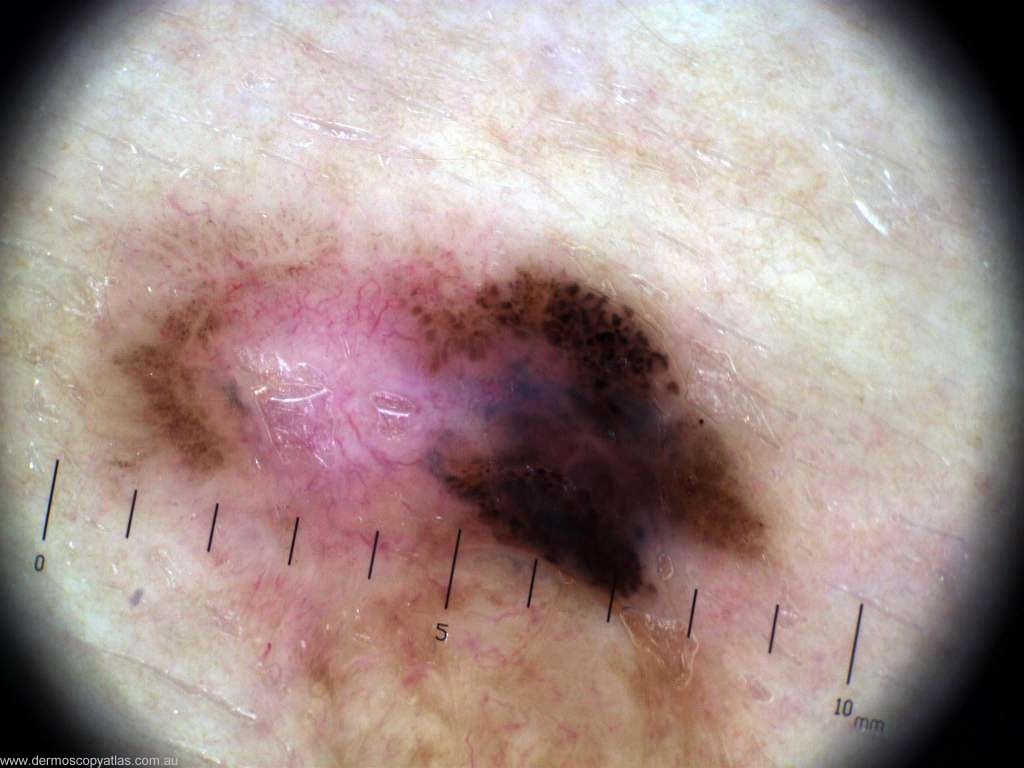

Case 5 25 year old female. No history. Lower back. Routine check.

Question: What do you think is the diagnosis? Consider Melanoma, BCC, Dysplastic nevus, Bowen's disease,Seborrhoeic keratosis and Combined nevus.

Answer: Histology: L2 (0.3mm) superficial spreading melanoma arising within a dysplastic compound naevus.